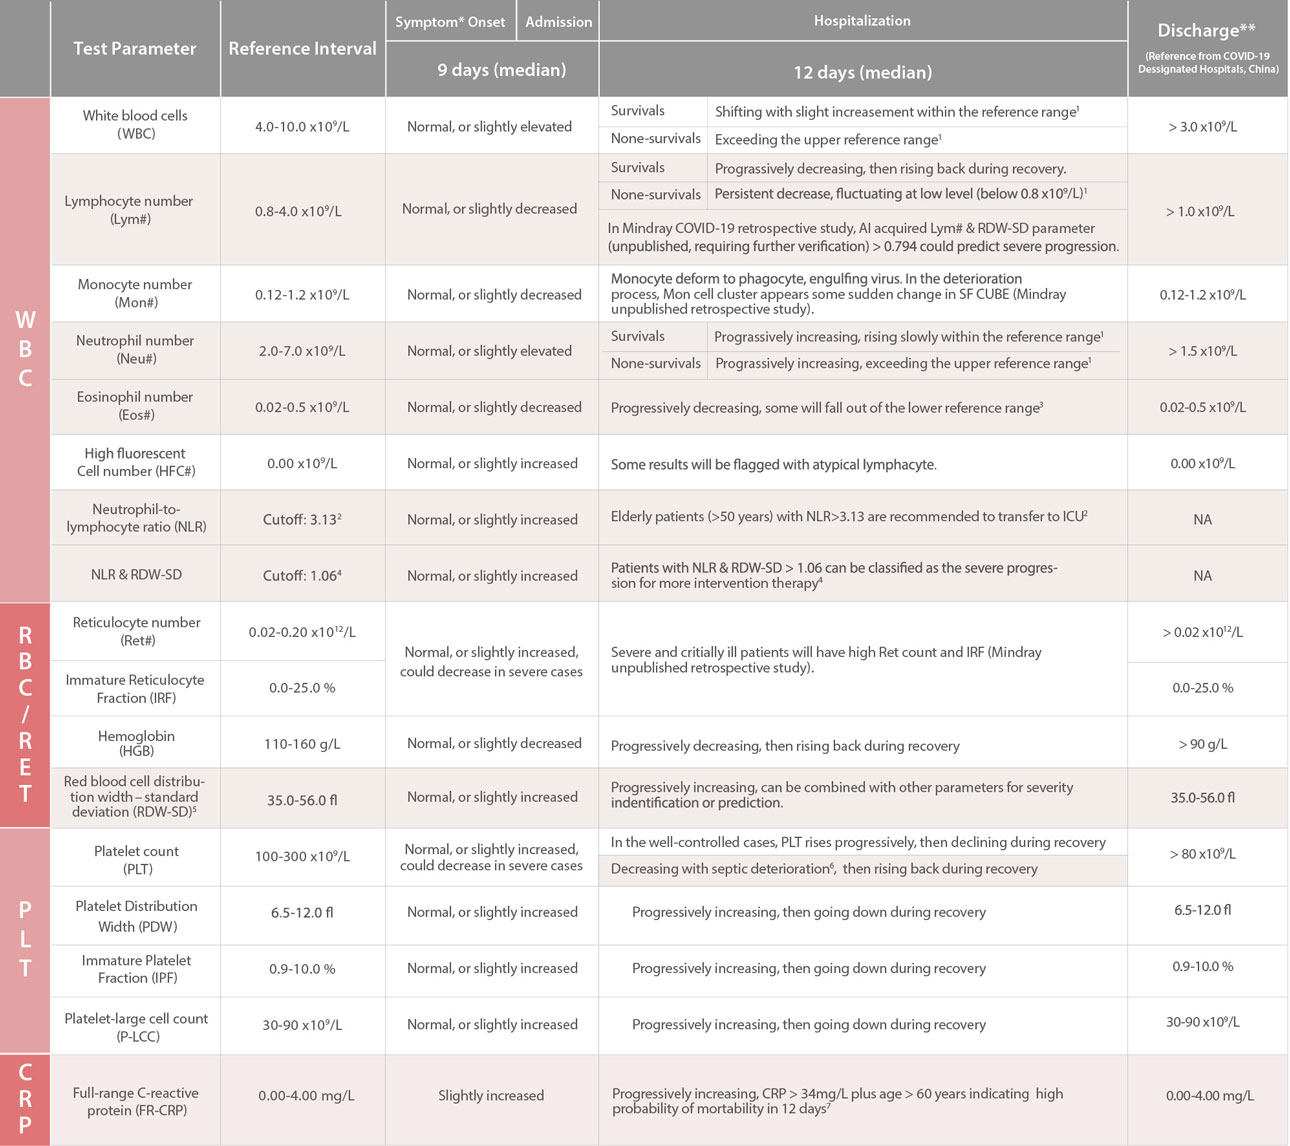

Hematology Test Indices

*Symtoms: fever, cough, breathing difficulties, headache, diarrhea

?

**Discharge: Under the premise that the patient's nucleic acid test result is negative for two consecutive days (alveolar lavage fluid is recommended8 )

?

?

CLIA Test Indices

Biochemistry Test Indices

[1]. Fei Zhou, Ting Yu, et al. Clinical course and risk factors for mortality of adult inpatients with COVID-19, a retrospective cohort study. Lancet (2020). doi: 10.1016/S0140-6736(20)30566-3

[2]. Jingyuan Liu, Yao Liu, Pan Xiang, et al. Neutrophil-to-Lymphocyte Ratio Predicts Severe Illness Patients with 2019 Novel Coronavirus in the Early Stage. Medrxiv. doi: 10.1101/2020.02.10.20021584

[3]. Jin-jin Zhang, Xiang Dong, Yi-yuan Cao, et al. Clinical characteristics of 140 patients infected with SARSCoV-2, Allergy. 2020 Feb 19. doi: 10.1111/all.14238.

[4]. Wang CZ, NLR&RDW-SD: Indices for Identifying Severe COVID-19 Patients (to be published officially). /en/presscenter/NLR_RDW-SD__Indices_for_Identifying_Severe_COVID-19_Patients.html

[5]. Ephrem G., Red Blood Cell Distribution Width Should Indeed Be Assessed with Other Inflammatory Markers in Daily Clinical Practice. Cardiology. 2013;124(1):61. doi: 10.1159/000345925.

[6]. G. Lippi, M. Plebani, B. Michael Henry, Thrombocytopenia is associated with severe coronavirus disease 2019 (COVID-19) infections: A meta-analysis, Clinica Chimica Acta (2020). doi: 10.1016/j.cca.2020.03.022

[7]. Jiatao Lu, Shufang Hu, Rong Fan, et al. ACP risk grade: a simple mortality index for patients with confirmed or suspected severe acute respiratory syndrome coronavirus 2 disease (COVID-19) during the early stage of outbreak, medRxiv. doi: 10.1101/2020.02.20.20025510

[8]. Xiao-Hong Yao, Zhi-Cheng He, Ting-Yuan Li, Hua-Rong Zhang, et al. Pathological evidence for residual SARS-CoV-2 in pulmonary tissues of a ready-for-discharge patient. Cell Research (2020) 0:1ŌĆō3. doi: 10.1038/s41422-020-0318-5